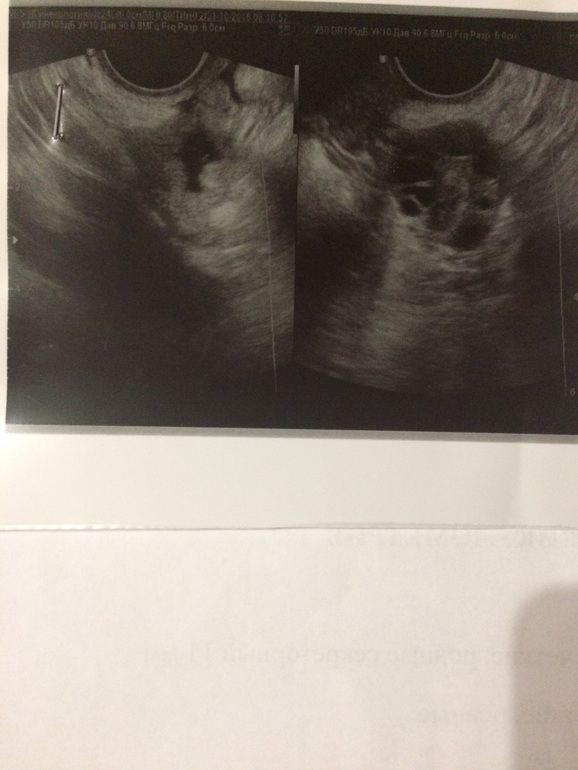

14 дц, ДФ в правом яичнике 21мм 16 дц, ЖТ 17 мм

Когда я задала вопрос такой же своему гинекологу, как отличить ЖТ от ДФ, она говорит это сразу видно, также у ЖТ есть признак, это кровоток вокруг (если правильно назвала), типа как на фото

14 дц, ДФ в правом яичнике 24*19 мм 15 дц, ЖТ 14*10мм

13 дц, проовулировавший фолликул 11мм